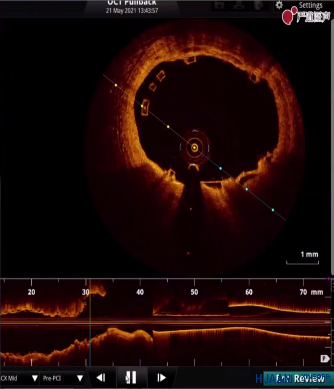

OCT提示11点方向支架贴壁不良

术中,葛均波院士先使用3.0*10mm切割球囊以6-8atm切割LCX狭窄病变,扩张满意之后选择Xinsorb 3.5-18mm可降解支架,精确定位于LCX近段,逐渐缓慢增加压力释放支架,最后以8atm释放支架,但造影提示支架近端左房支对侧管壁支架球囊扩张不充分,有小切记表现,为明确支架贴壁情况,使用OCT进行腔内影像检查评估。OCT检查结果提示,近段病变支架贴壁不良,尤其有分支血管部位。

使用3.5*12mm后扩张球囊对支架远端以14atm进行后扩张,近端以18atm进行后扩张。扩张后,再次复查OCT,虽然用3.5*12mm后扩张球囊打到18atm,支架贴壁情况明显改善,但左房支开口对侧仍有个别支架梁贴壁不佳,但由于后扩张压力已经比较大,其余部位已充分贴壁,故不再反复后扩张。OCT对评估支架贴壁不良起到了很大的帮助。

OCT提示2点方向仍有个别支架梁贴壁不良